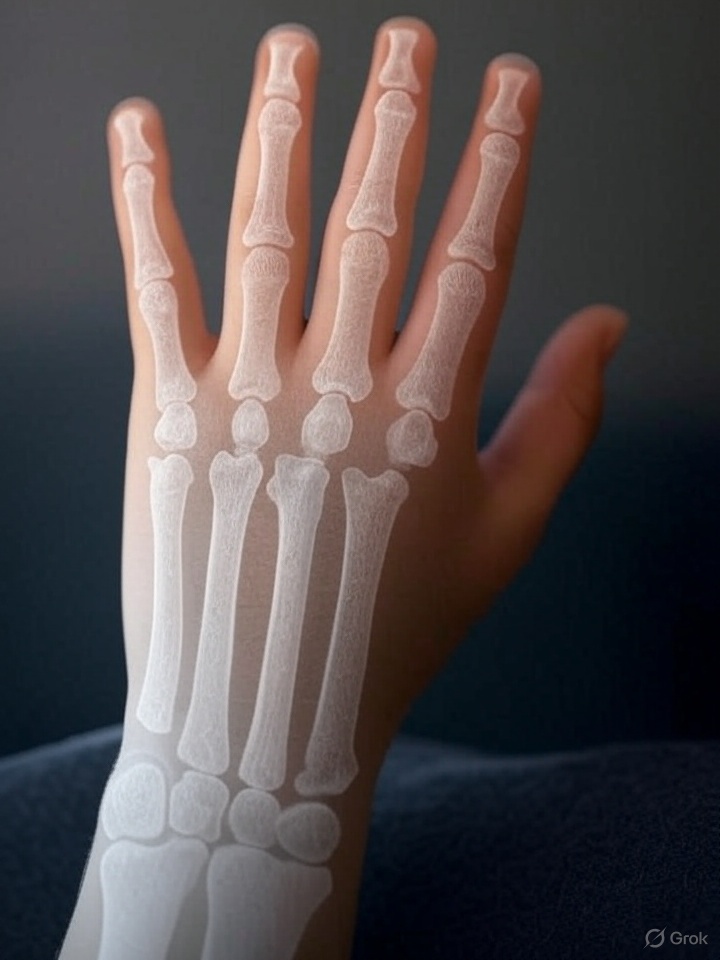

Para comprender el valor de la inteligencia artificial en este contexto, es necesario recordar cómo se ha evaluado históricamente la maduración infantil. Durante décadas, los médicos se han basado en el análisis de radiografías de la mano izquierda. Esta parte del cuerpo, rica en huesos y centros de crecimiento, ofrece una imagen muy representativa de la madurez biológica de un menor.

¿Por qué la mano izquierda? Es una convención establecida para unificar los criterios de evaluación. Lo importante es que en esta mano se puede observar, con claridad, cómo avanza la osificación de los huesos, un proceso que indica en qué fase de desarrollo está una persona joven.

Este método se perfeccionó en el siglo XX gracias al trabajo de investigadores como Todd y sus discípulos Greulich y Pyle, quienes elaboraron en 1959 un atlas de radiografías canónicas clasificadas por edad y sexo. Su objetivo era proporcionar una guía visual y accesible para que los evaluadores pudieran comparar la mano izquierda de un paciente y estimar su “edad ósea”, obteniendo así una medida cuantitativa de la maduración biológica.